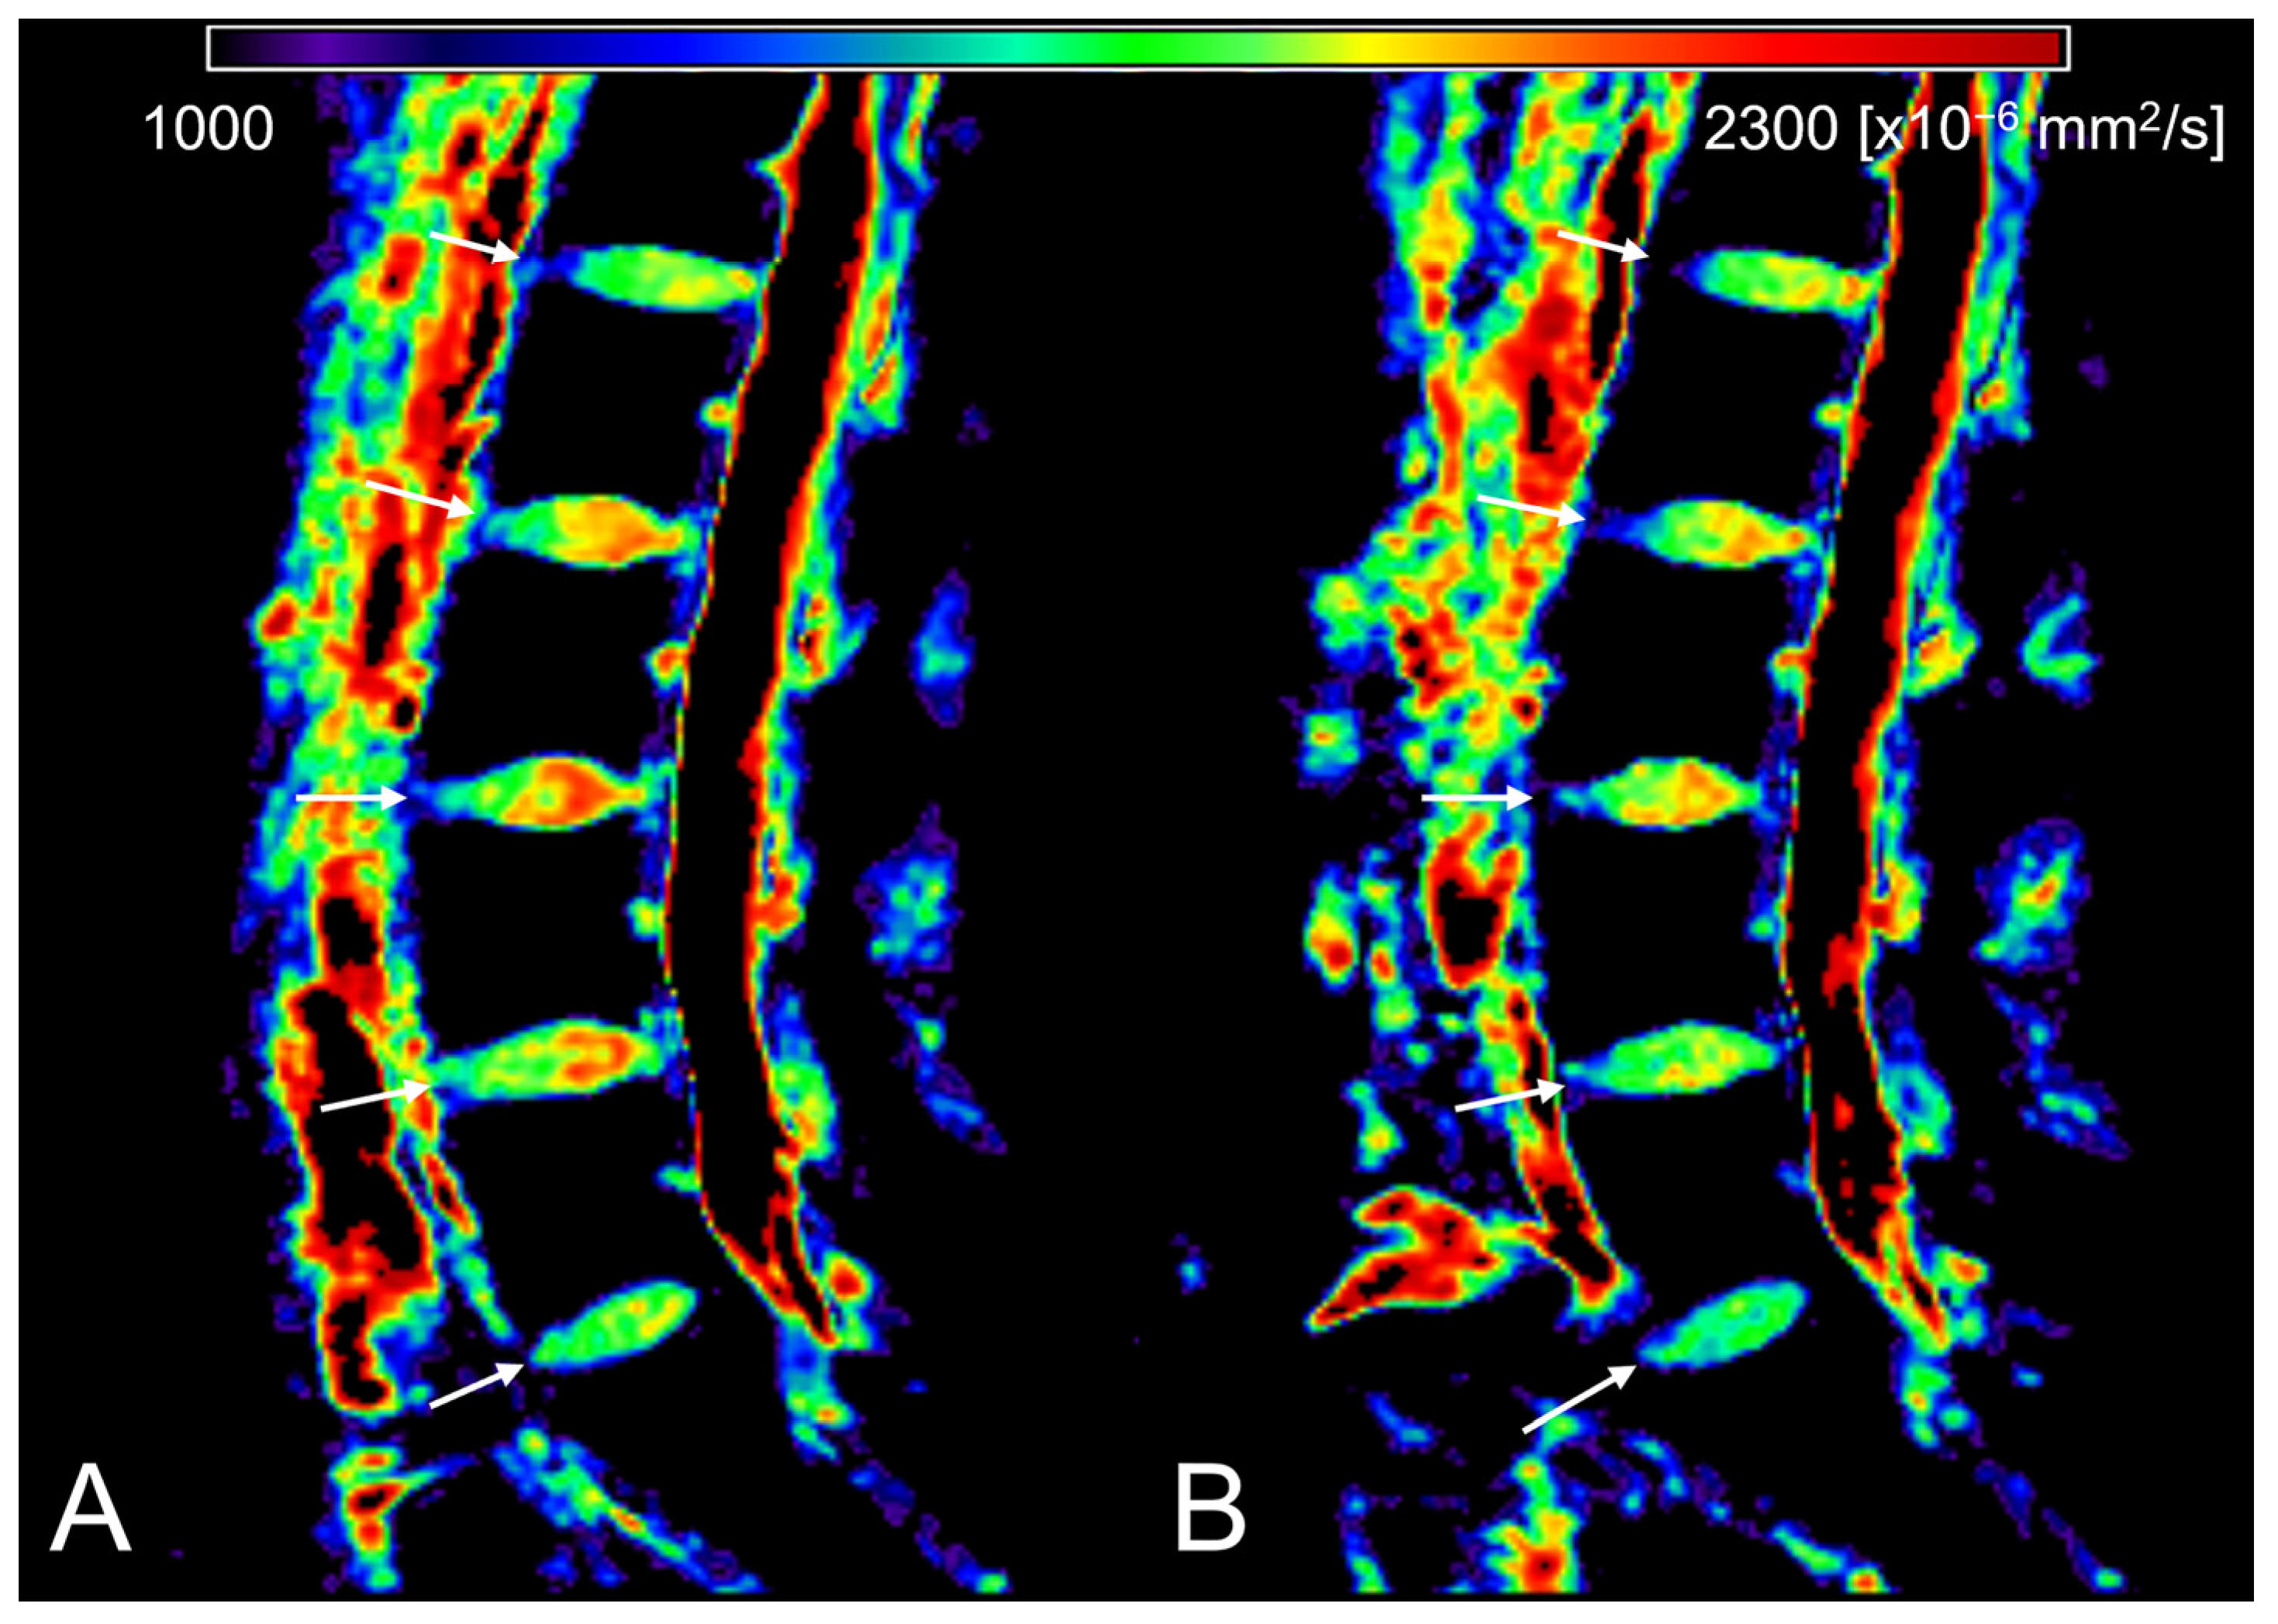

| ADC [×10−6 mm2/s] | Morning | 1784.633 ±124.527 | 1744.867 ±84.098 | 1810.641 ±116.277 | 1849.257 ±89.464 | 1776.74 1 ± 168.954 | 1738.196 ±127.040 |

| (1328.54 − 2005.07) | (1633.64 − 1909.40) | (1507.33 − 2005.07) | (1689.26 − 1986.82) | (1328.54 − 1922.59) | (1345.55 − 1872.46) | ||

| Evening | 1761.456 ±134.130 | 1728.474 ±63.042 | 1769.122 ±142.371 | 1824.274 ±103.646 | 1751.606 ±183.742 | 1733.224 ±142.604 | |

| (1247.46 − 1972.04) | (1605.50 − 1849.15) | (1356.50 − 1926.90) | (1602.80 − 1972.04) | (1247.46 − 1897.12) | (1376.50 − 1912.06) | ||

| N | 84 | 17 | 17 | 17 | 16 | 17 | |

| p | <0.001 | 0.101 | 0.002 | 0.025 | 0.056 | 0.741 | |